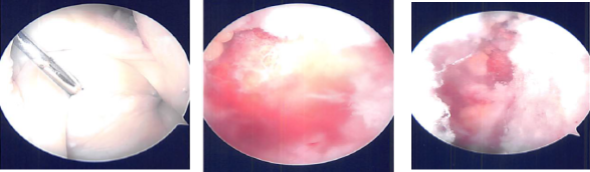

Intraoperative images

There was labral tearing along the anterior superior part along with tenting of the superior labrum and the biceps. An inferior portal was made with the use of a spinal needle. Shaver was introduced due to some debridement of the labrum of the biceps. Examination showed type 2 SLAP tears.

The fixation of labral tapes and to place these labral tapes into the labrum was found to be adequate. Picture was taken. The shoulder was debrided. Shoulder was swollen in the process and it was decided not to do a subacromial examination at the moment considering the symptoms from the labrum.